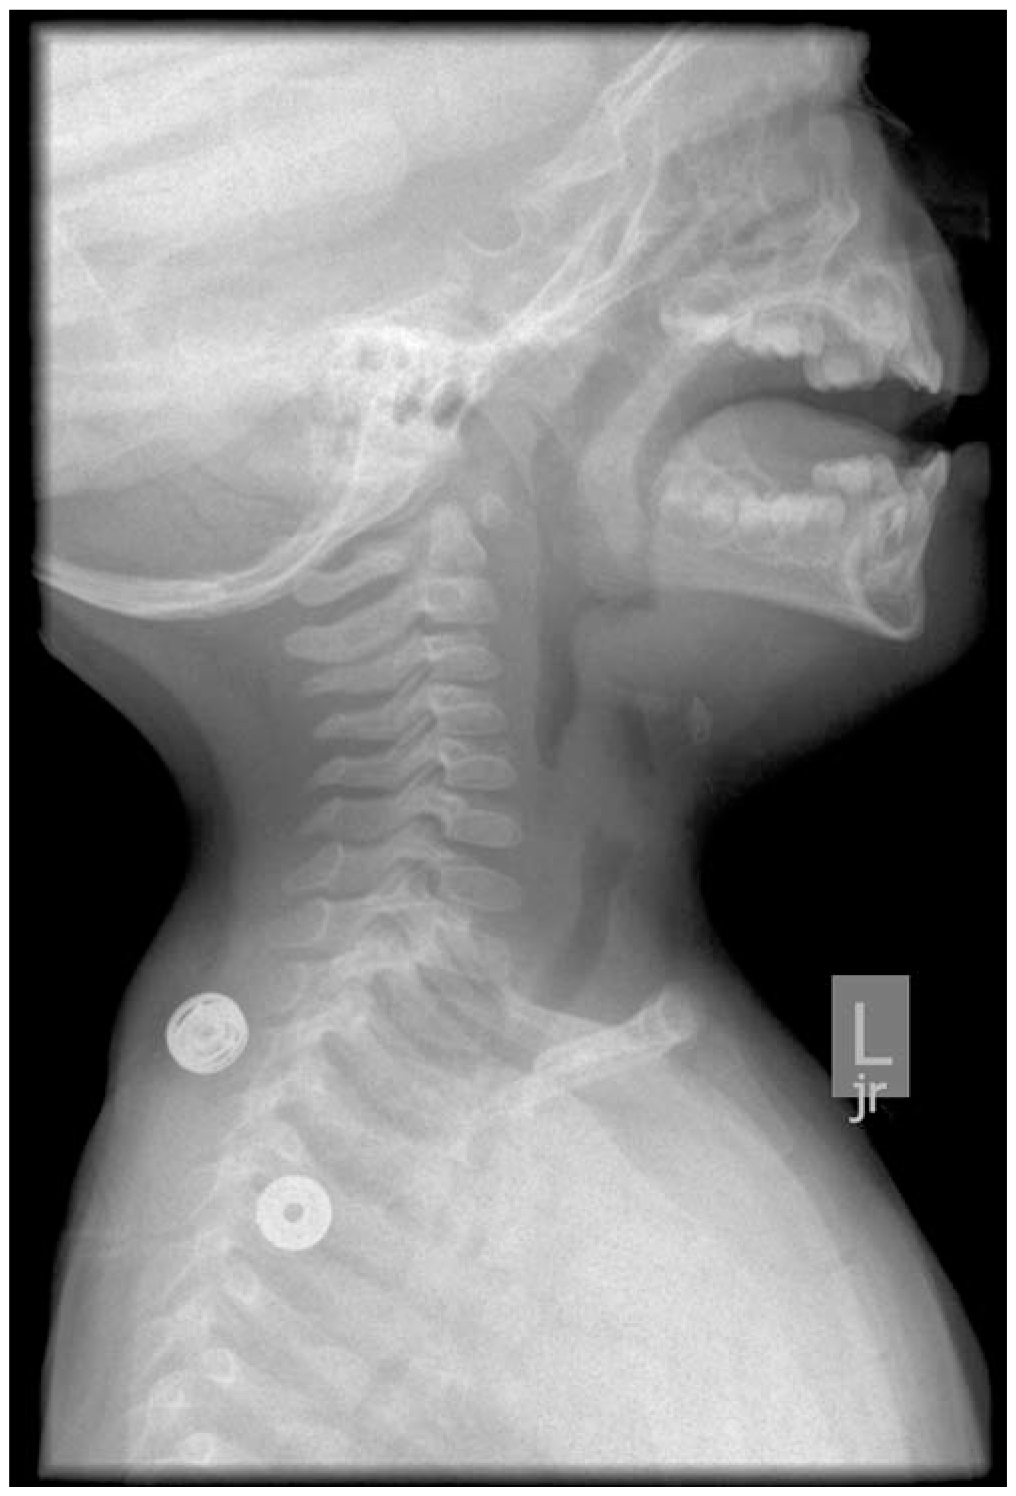

Pediatric Upper Airway Obstruction

- Evidence that imaging (radiographs, computed tomography, magnetic resonance imaging) should be reserved for selected patients

- Evidence that procedural intervention may not always be required in cases of peritonsillar and retropharyngeal abscesses

- Enhanced understanding of epiglottitis pathophysiology, diagnosis, and treatment